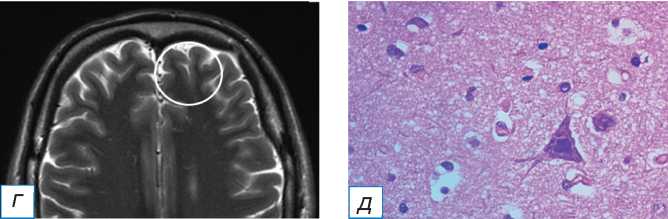

У 2 пациентов с ФКД теменной локализации зона гипометаболизма 18F-ФДГ не совпадала с локализацией структурных изменений на МРТ, но располагалась в соседних участках вещества мозга (рис. 2, 3). При проведении этим пациентам стерео-ЭЭГ-ВМ эпилептиформная активность определялась в зоне выявленных структурных изменений и не регистрировалась в зоне метаболических изменений.

Рис. 2. Совмещённая позитронно-эмиссионная томография с магнитно-резонансной томографией (ПЭТ/МРТ) головного мозга с 18F-ФДГ пациента с фокальной кортикальной дисплазией в левой теменной доле: а (совмещённое изображение ПЭТ-МРТ в аксиальной плоскости) — отсутствие признаков гипометаболизма 18F-ФДГ в области фокальной кортикальной дисплазии (стрелка); б (Т2-ВИ в аксиальной плоскости) — участок повышения интенсивности МР-сигнала и снижения серо-белой демаркации в левой теменной доле (стрелка); в (совмещённое изображение ПЭТ-МРТ в аксиальной плоскости) — зона гипометаболизма 18F-ФДГ в парамедианных отделах левой лобной доли (окружность); г (Т2-ВИ в аксиальной плоскости) — отсутствие патологических структурных изменений в зоне гипометаболизма 18F-ФДГ (окружность).